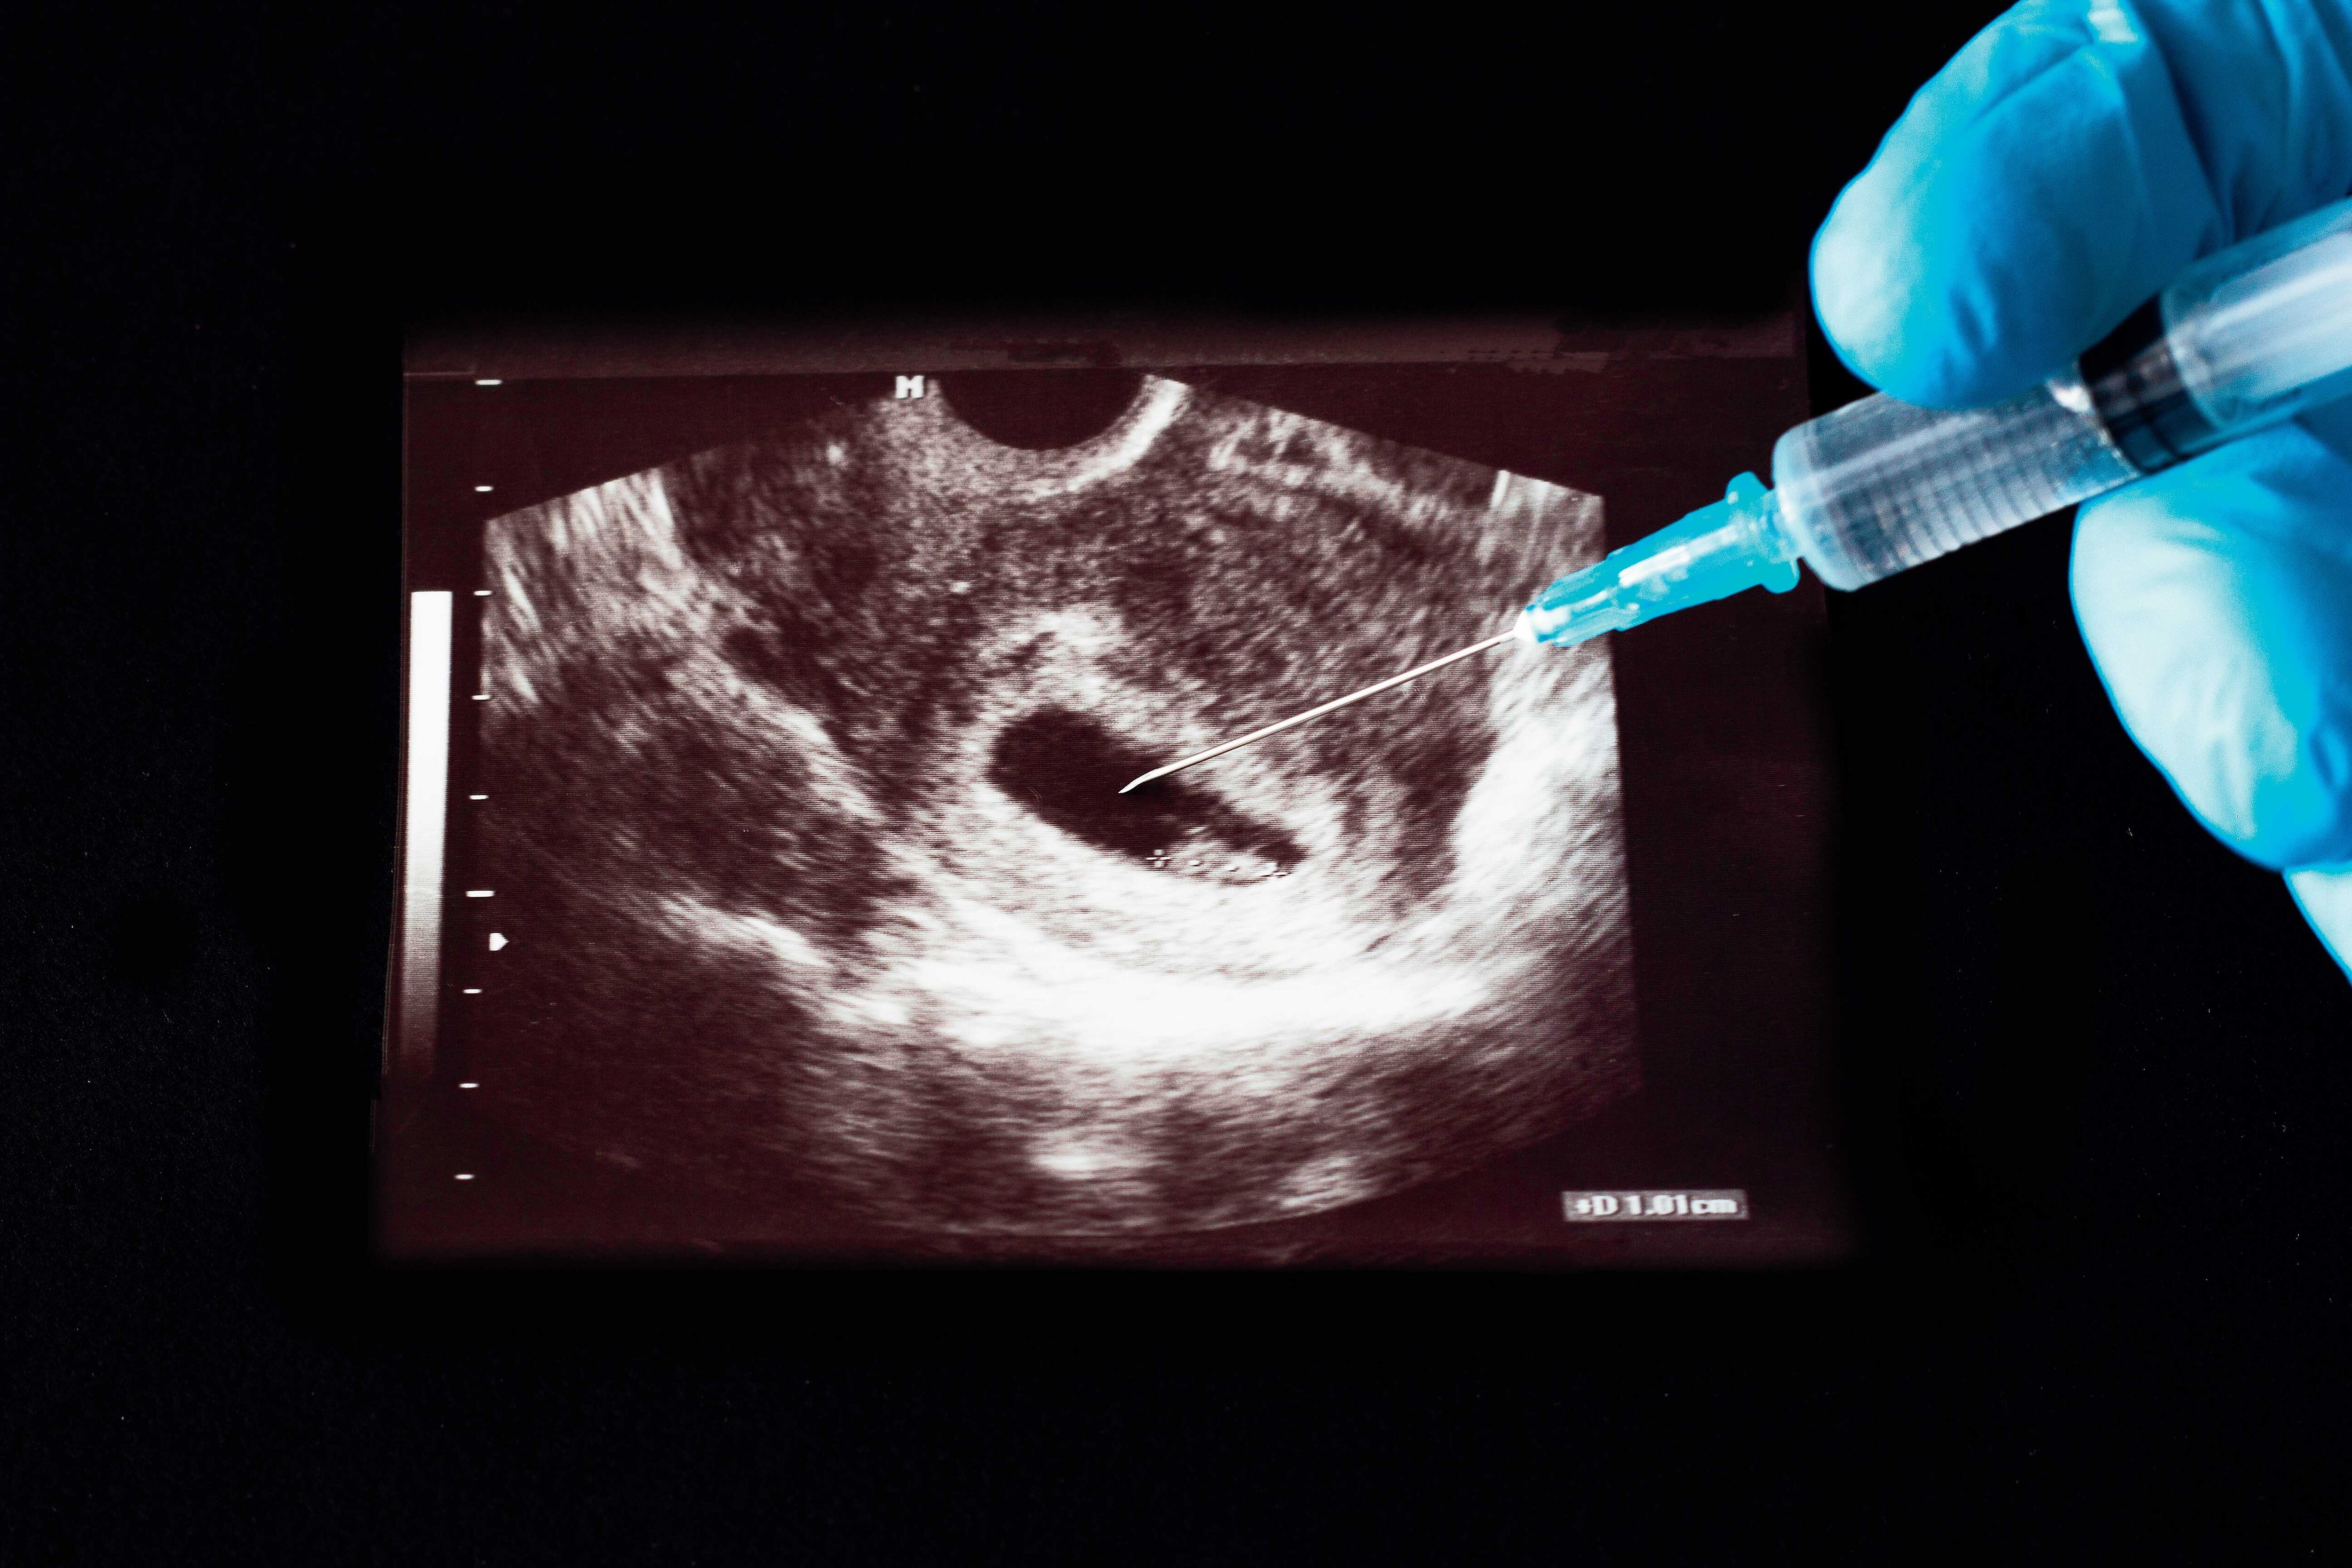

La figura del aborto terapéutico o aborto impune está establecida en el artículo 121 del Código Penal costarricense desde 1970. Antes de la publicación de la norma técnica, era la única herramienta en manos del personal de salud. En más de una ocasión, los médicos, principalmente, expresaron dudas sobre su aplicación ante la falta de un protocolo para aclarar las condiciones en las cuales debían o no interrumpir el embarazo cuando mediaban razones de salud de la madre.

La Norma Técnica para el Procedimiento Médico Vinculado con el Artículo 121 del Código Penal salió publicada como decreto ejecutivo el 17 de diciembre del 2019.

La precedieron cuatro años de trabajo técnico y dos demandas contra Costa Rica ante la Comisión Interamericana de Derechos Humanos (CIDH), presentadas en el 2015 por dos mujeres, identificadas como ‘Ana’ y ‘Aurora’, a quienes se les negó el procedimiento. Ellas denunciaron las dificultades que vivieron en hospitales públicos al pedir la interrupción de su embarazo.

Después de la publicación de la norma técnica, el Ministerio de Salud aprobó en diciembre del 2020 el protocolo para atender las solicitudes del procedimiento en los hospitales de la CCSS. En marzo pasado, solo un hospital privado había presentado su protocolo para ser sometido a aprobación. El Ministerio tiene la responsabilidad de vigilar la aplicación de la norma.

Solo se han realizado dos interrupciones terapéuticas del embarazo aplicando la norma técnica. El año pasado, los hospitales públicos atendieron seis solicitudes: cuatro se presentaron en el Hospital San Juan de Dios, de las cuales solo dos procedimientos fueron aprobados y realizados después de cumplir los pasos establecidos en la norma.